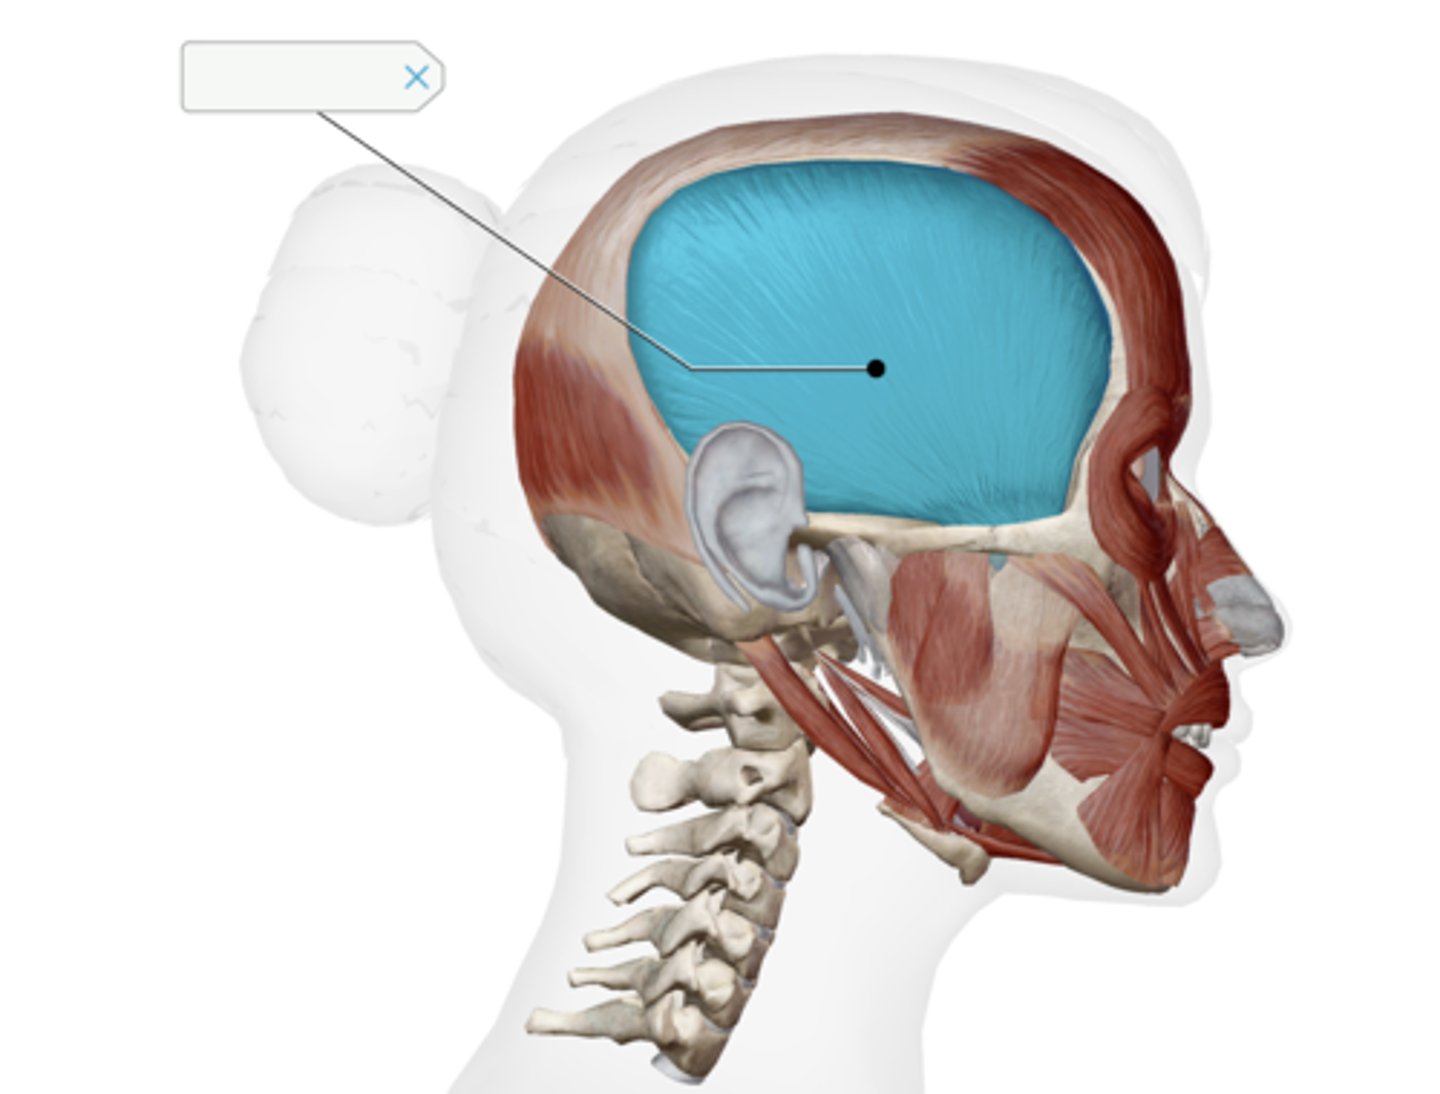

Temporalis